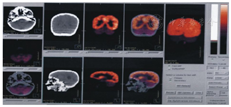

15例患儿中,临床诊断脑瘫(共济失调型)10例(67%),主要临床资料见表3。其中男、女各5例;起病年龄1~10(5.5±4.5)个月;首次住院年龄4个月~3岁6个月,康复治疗疗程3~58个月,康复治疗不足1年者均临床随访至少1年观察病情无进行性恶化以排除遗传代谢性疾病等神经系统进展性疾病;10例患者均在婴儿期起病,首发症状为运动发育落后,肌张力低下,均有下肢共济失调表现,部分伴躯干或/和双上肢受累,9例伴有智能障碍;10例围生期危险因素有母孕早期上呼吸道感染、先兆流产、羊水少、胎儿宫内窘迫、胎膜早破、产程延长、黄疸等;7例头颅CT或MRI提示存在小脑半球萎缩;3例头颅MRI未发现小脑结构异常,其中2例行头颅PET-CT提示存在小脑神经元功能降低(图1、图2)。6例行血、尿代谢分析未见特异性异常。3例行染色体核型分析未见异常。分析10例共济失调型脑瘫患者康复治疗前后粗大运动功能测试量表(GMFM)总分及Gesell发育量表5个能区DQ,提示康复治疗前GMFM总分为44.15±20.41,康复治疗后GMFM总分为56.42±15.65,二者比较差异有统计学意义(t=-3.121,P<0.05);而Gesell发育量表社会适应、大运动、精细运动、语言及个人社交5个能区DQ,治疗前分别为37.47±14.47、35.23±17.23、37.06±11.51、40.69±12.10、40.41±15.79,治疗后分别为39.44±16.29、28.27±14.65、35.96±10.76、40.26±14.20、38.61±11.95,其中治疗后大运动能区DQ较治疗前下降,差异有统计学意义(t=2.75,P<0.05),余功能区治疗前后比较差异均无统计学意义(P均>0.05),见表4。

Brain positron emission tomography and computer tomography of the patient No.10,showing diffuse decreased radioactive distribution in bilateral cerebellar hemisphere

Brain positron emission tomography and computer tomography of the patient No.10,showing the radioactive ratio of bilateral cerebellar hemispheres to bilateral temporal lobes was about 0.61

共济失调型脑瘫占所有脑瘫类型的5%~10%[2],属慢性非进行性小脑共济失调范畴,并有报道其占据欧洲世界卫生组织地区儿童共济失调患病率的重要构成部分[14]。据估计大约50%共济失调型脑瘫呈常染色体隐性遗传,McHale等[15]对1个有4例共济失调脑瘫患者的家系利用343个荧光标记多态标志物进行全基因组分析提示致病基因定位在9p12-q12。本组10例共济失调型脑瘫患儿围生期危险因素多样,其与该病的相关性尚未明确,虽部分患者曾行染色体核型分析,血、尿代谢分析未见异常,仍不能排除遗传因素所致。日后对于诊断共济失调型脑瘫患者,有条件者可行DNA芯片检测或多重连接探针扩增技术等基因检测手段以进一步寻找遗传证据;确定相关致病基因可能有助于产前诊断或婚前检查的开展,并可提高对该病的认识。10例中7例头颅MRI或CT提示存在小脑发育不良或小脑萎缩,其中2例在婴儿早期影像学表现不明显,后期复查提示小脑萎缩,患者临床病情相对静止,运动功能缓慢进步,无明显倒退表现;3例患者头颅MRI无明显小脑结构异常,其中2例行头颅PET-CT提示存在小脑神经元代谢功能降低。因此,考虑慢性非进行性小脑共济失调患者多有小脑结构或功能异常,但早期影像学表现可能不明显,临床工作中应注意根据患儿病情定期复查头颅神经影像学检查以明确诊断;且在高度怀疑小脑病变时,即使头颅MRI无阳性发现,可进一步行头颅PET-CT检查以了解小脑神经元代谢功能情况。PET-CT在神经系统疾病的应用日益广泛,大脑皮质中细微的糖代谢、血流等变化可在屏幕上出现不同的图像,凡代谢率高的组织或病变,在PET-CT上呈现明亮的高代谢亮信号,凡代谢率低的组织或病变在PET-CT上呈现出低代谢暗信号[16]。